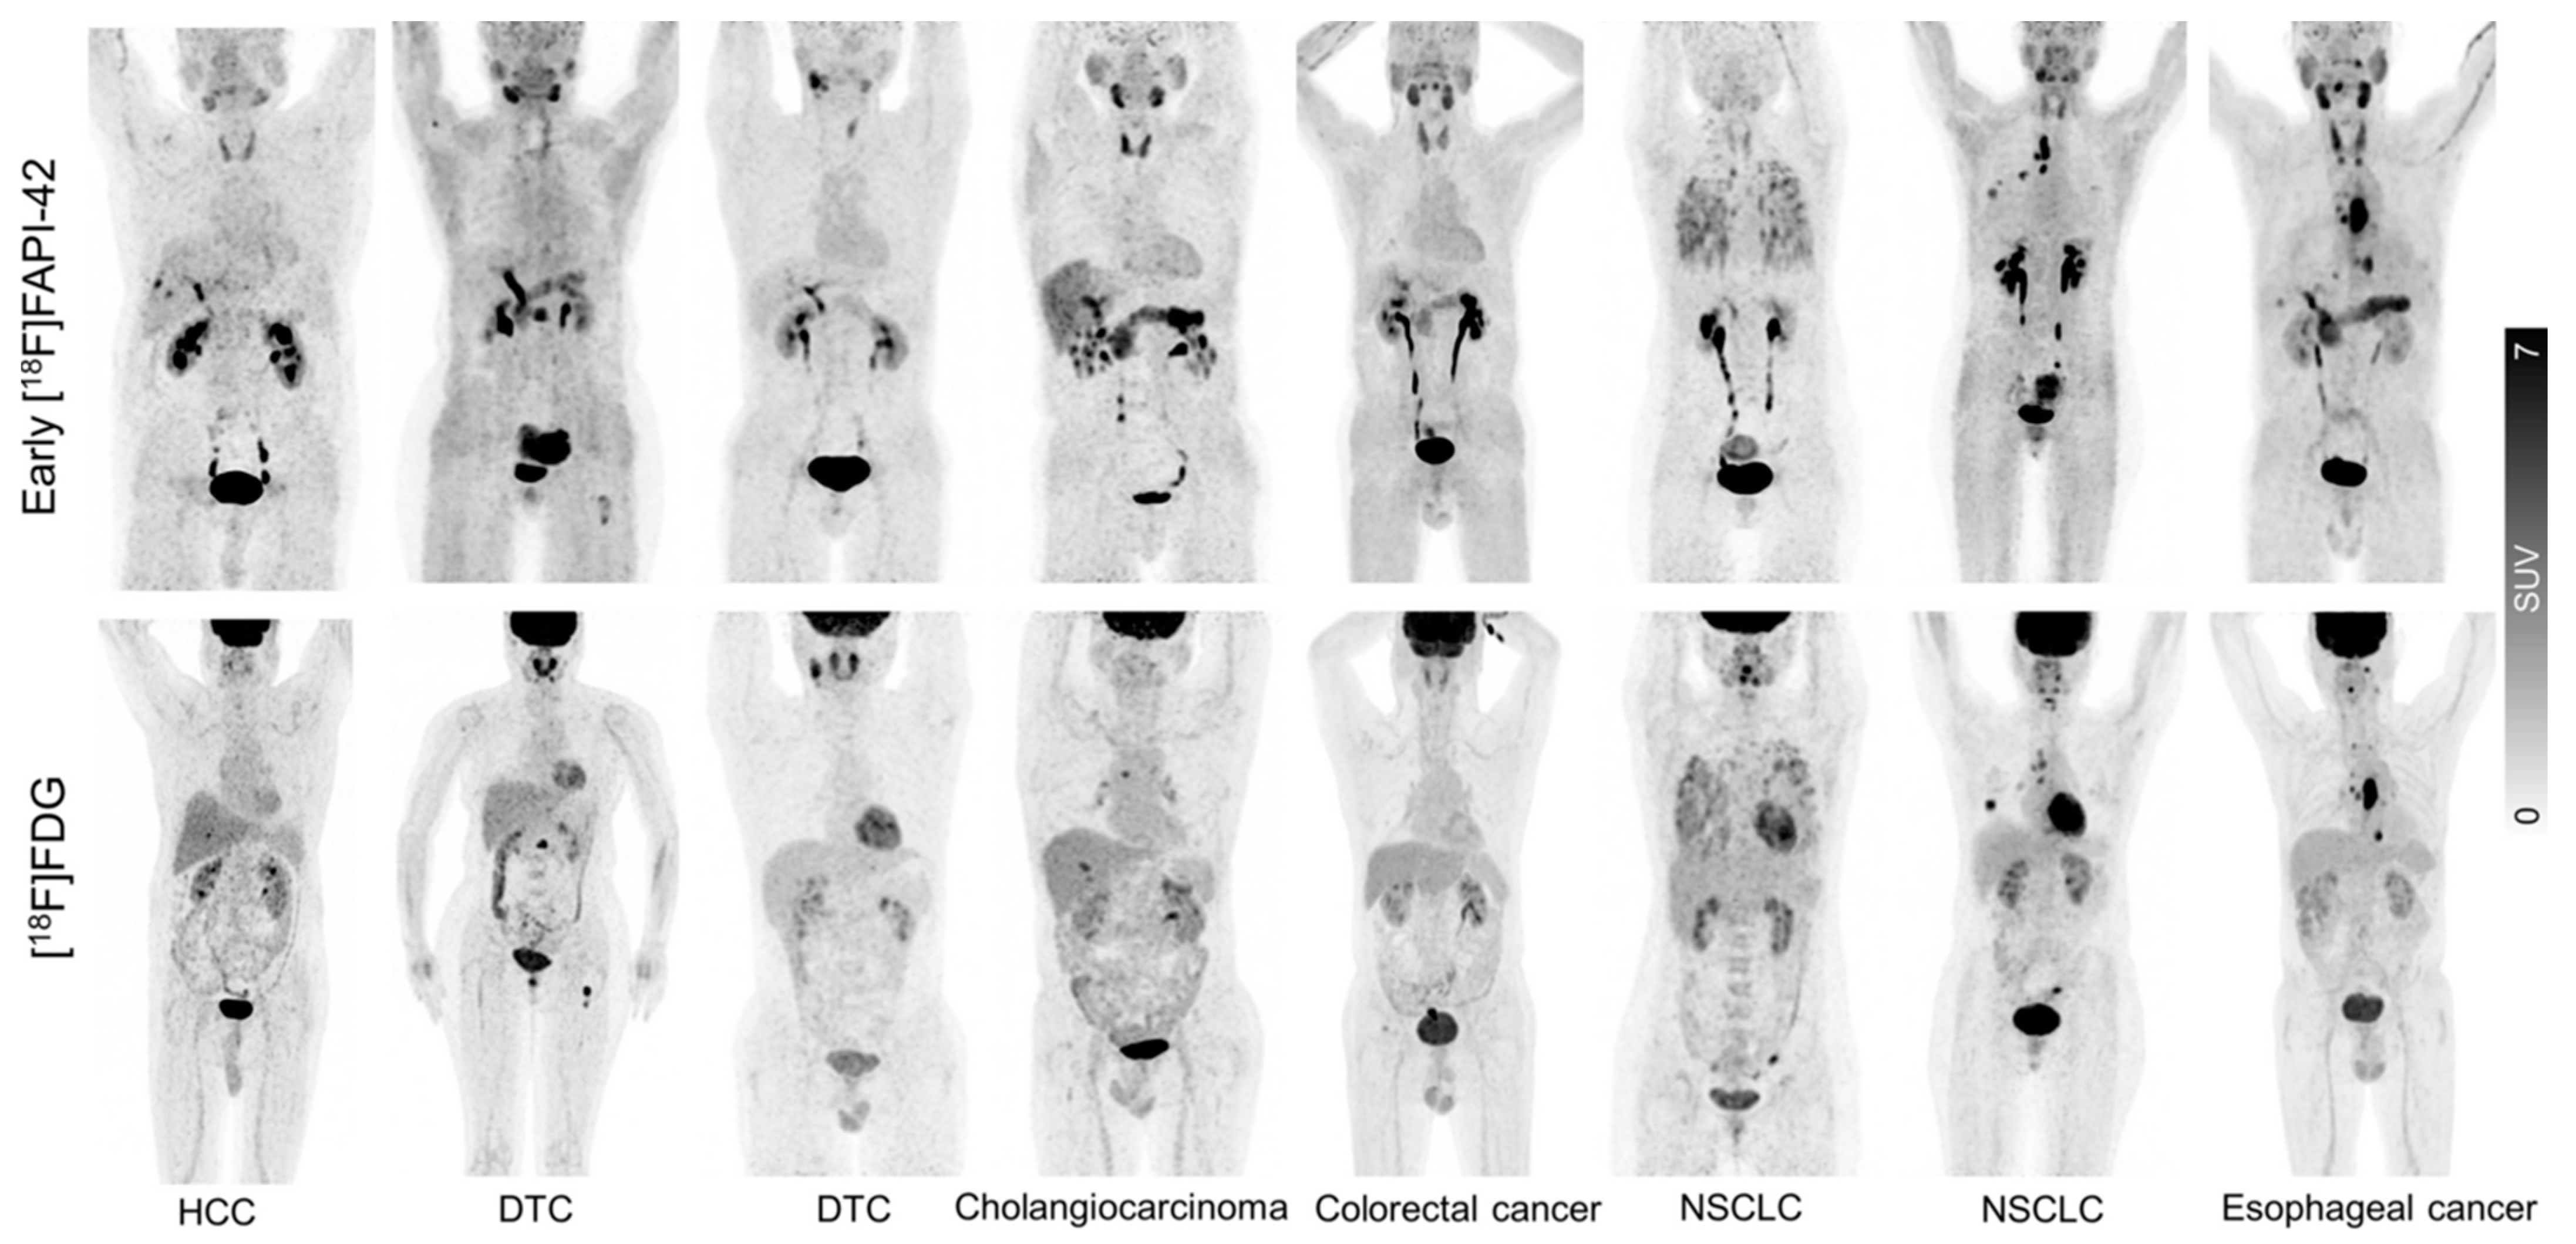

- Hu, K.; Wang, L.; Wu, H.; Huang, S.; Tian, Y.; Wang, Q.; Xiao, C.; Han, Y.; Tang, G. [18F]FAPI-42 PET Imaging in Cancer Patients: Optimal Acquisition Time, Biodistribution, and Comparison with [68Ga]Ga-FAPI-04. Eur. J. Nucl. Med. Mol. Imaging 2022, 49, 2833–2843. [Google Scholar] [CrossRef]

- Mu, X.; Mo, B.; Qin, J.; Li, Z.; Chong, W.; Zeng, Y.; Lu, L.; Zhang, L.; Fu, W. Comparative Analysis of Two Timepoints on [18F]FAPI-42 PET/CT in Various Cancers. Eur. J. Hybrid Imaging 2023, 7, 27. [Google Scholar] [CrossRef]